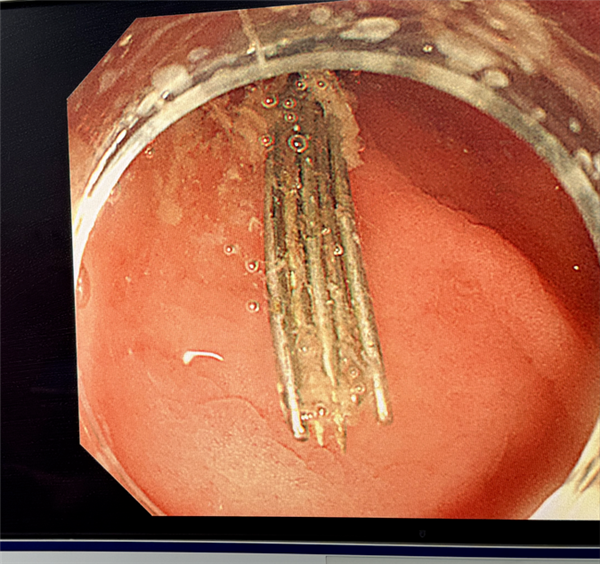

内镜缓缓进入胃腔,屏幕上的画面让人不寒而栗:

多根绣花针散落在胃内,绣花针细小、光滑、数量多,且部分紧贴胃壁,操作稍有不慎,就可能造成二次损伤,手术难度极大。

好在医生凭借丰富的临床经验和精湛操作,经过三个小时的连续奋战,最终12根长4–5厘米的绣花针被完整、安全地全部取出。